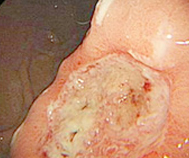

• 无痛胃镜

• 无痛肠镜

• 胶囊内镜